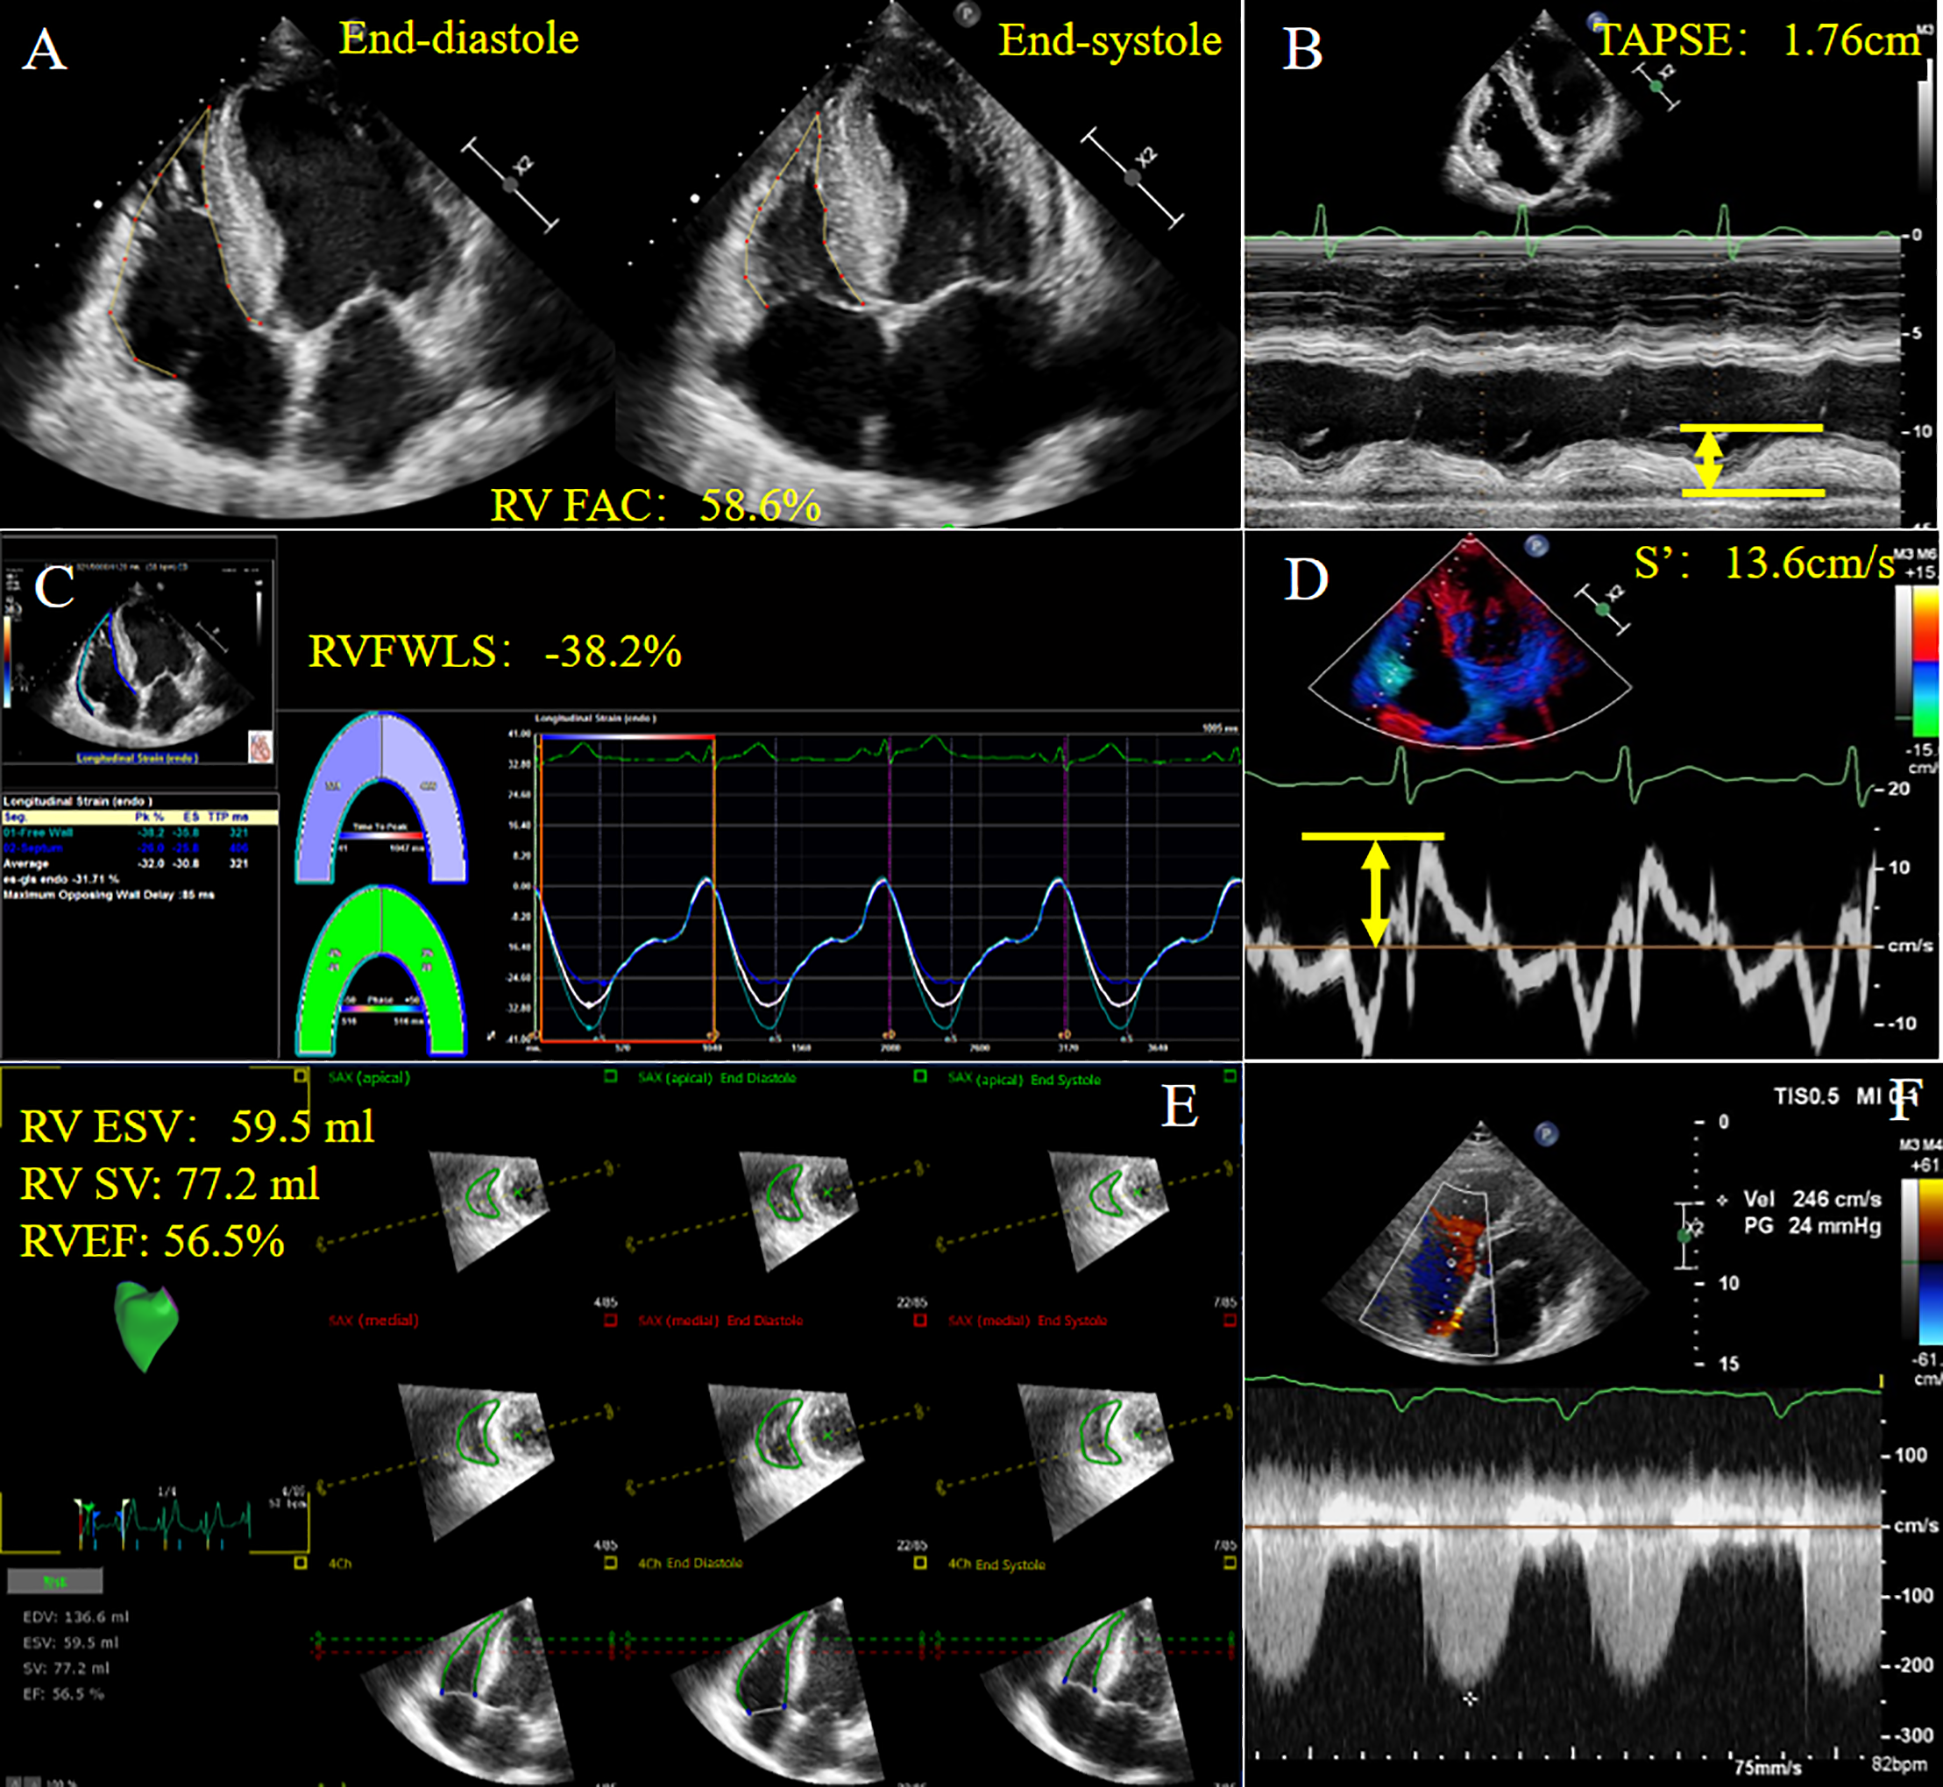

Novel methods to account for RV-PA coupling, such as three-dimensional echocardiography (3DE) and RV strain, are gaining increasing attention. Acquisition of ESV/SV by 3DE using offline software has been shown to be associated with invasively measured RV-PA coupling from cardiac catheterization in patients with pulmonary hypertension (29). 3DE can be performed postoperatively to avoid assessment of TAPSE and RV geometric hypothesis. The ratio of RV free wall longitudinal strain (RVFWLS) obtained by speckle-tracking echocardiography (STE) to PASP has also been used in clinical practice (30), and has shown its potential value in pulmonary hypertension patients compared with conventional echocardiographic parameters (9). Apart from the above-mentioned indices, the ratios between fractional area change (FAC), right ventricular ejection fraction (RVEF) or tricuspid annular peak systolic velocity (S′) measured by tissue Doppler imaging and PASP or RVSP are less commonly used (13, 31). Non-invasive measurement of RV function and RV-PA coupling parameters are shown in Figure 2.

Figure 2

Non-invasive measurement of RV function and RV-PA coupling parameters derived from echocardiography in a patient with HFpEF. (A) RVFAC; (B) TAPSE; (C) RVFWLS; (D) S′; (E) 3D-TTE derived RV ESV, RV SV, RVEF; (F) Tricuspid regurgitation spectrum. HFpEF, heart failure with preserved ejection fraction; RVFAC, right ventricular fractional area change; TAPSE, tricuspid annular plane systolic excursion; RVFWLS, right ventricular free wall longitudinal strain; S′, tricuspid annular systolic velocity; ESV, end systolic volume; SV, stroke volume; RVEF, right ventricular ejection fraction. Yellow arrows represent measurements for parameters.